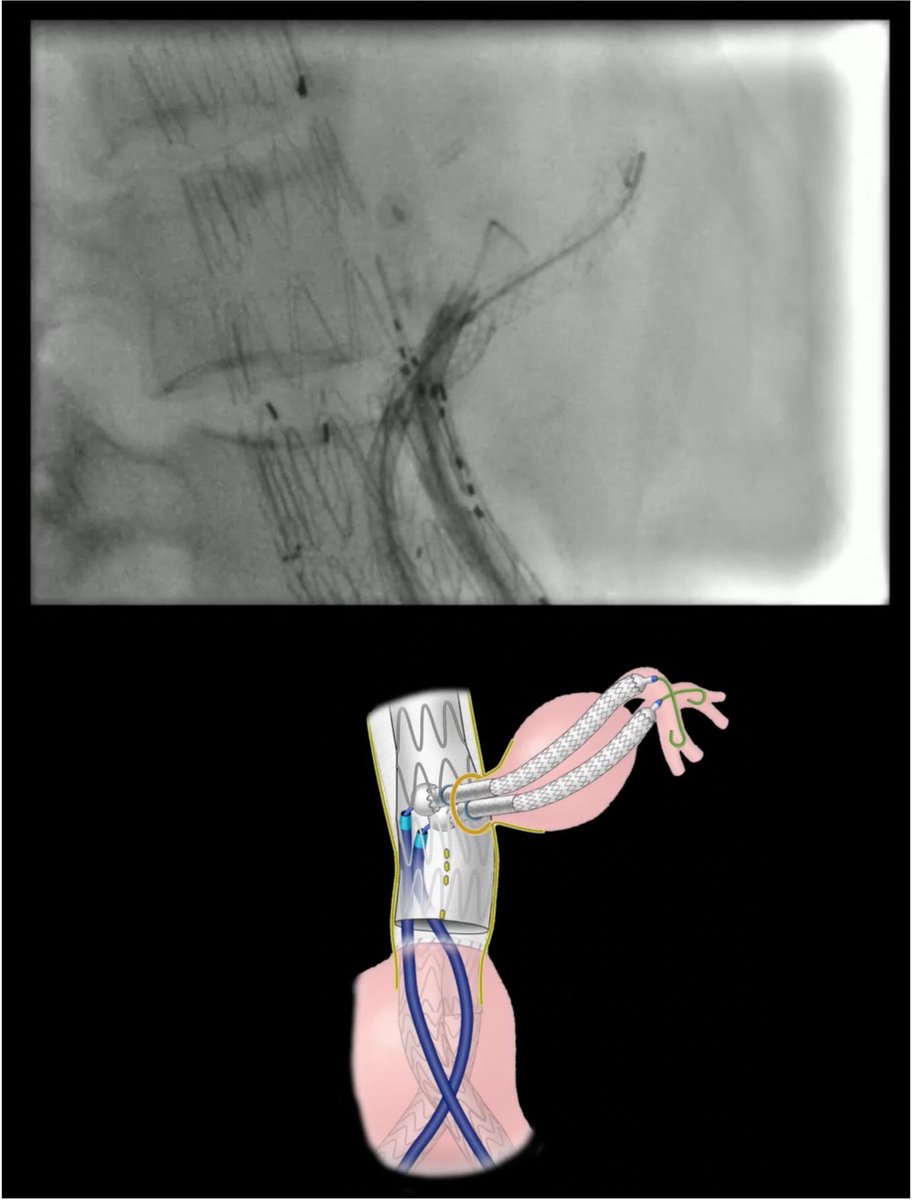

Another amazing #HIDI on #techniquetuesday from @SukguH @usc_vascular on in-situ laser fenestration! Some serious #aortaED right here, don't miss out! jvscit.org/article/S2468-… What other "how I do it" articles would @VascularSVS like to see published?